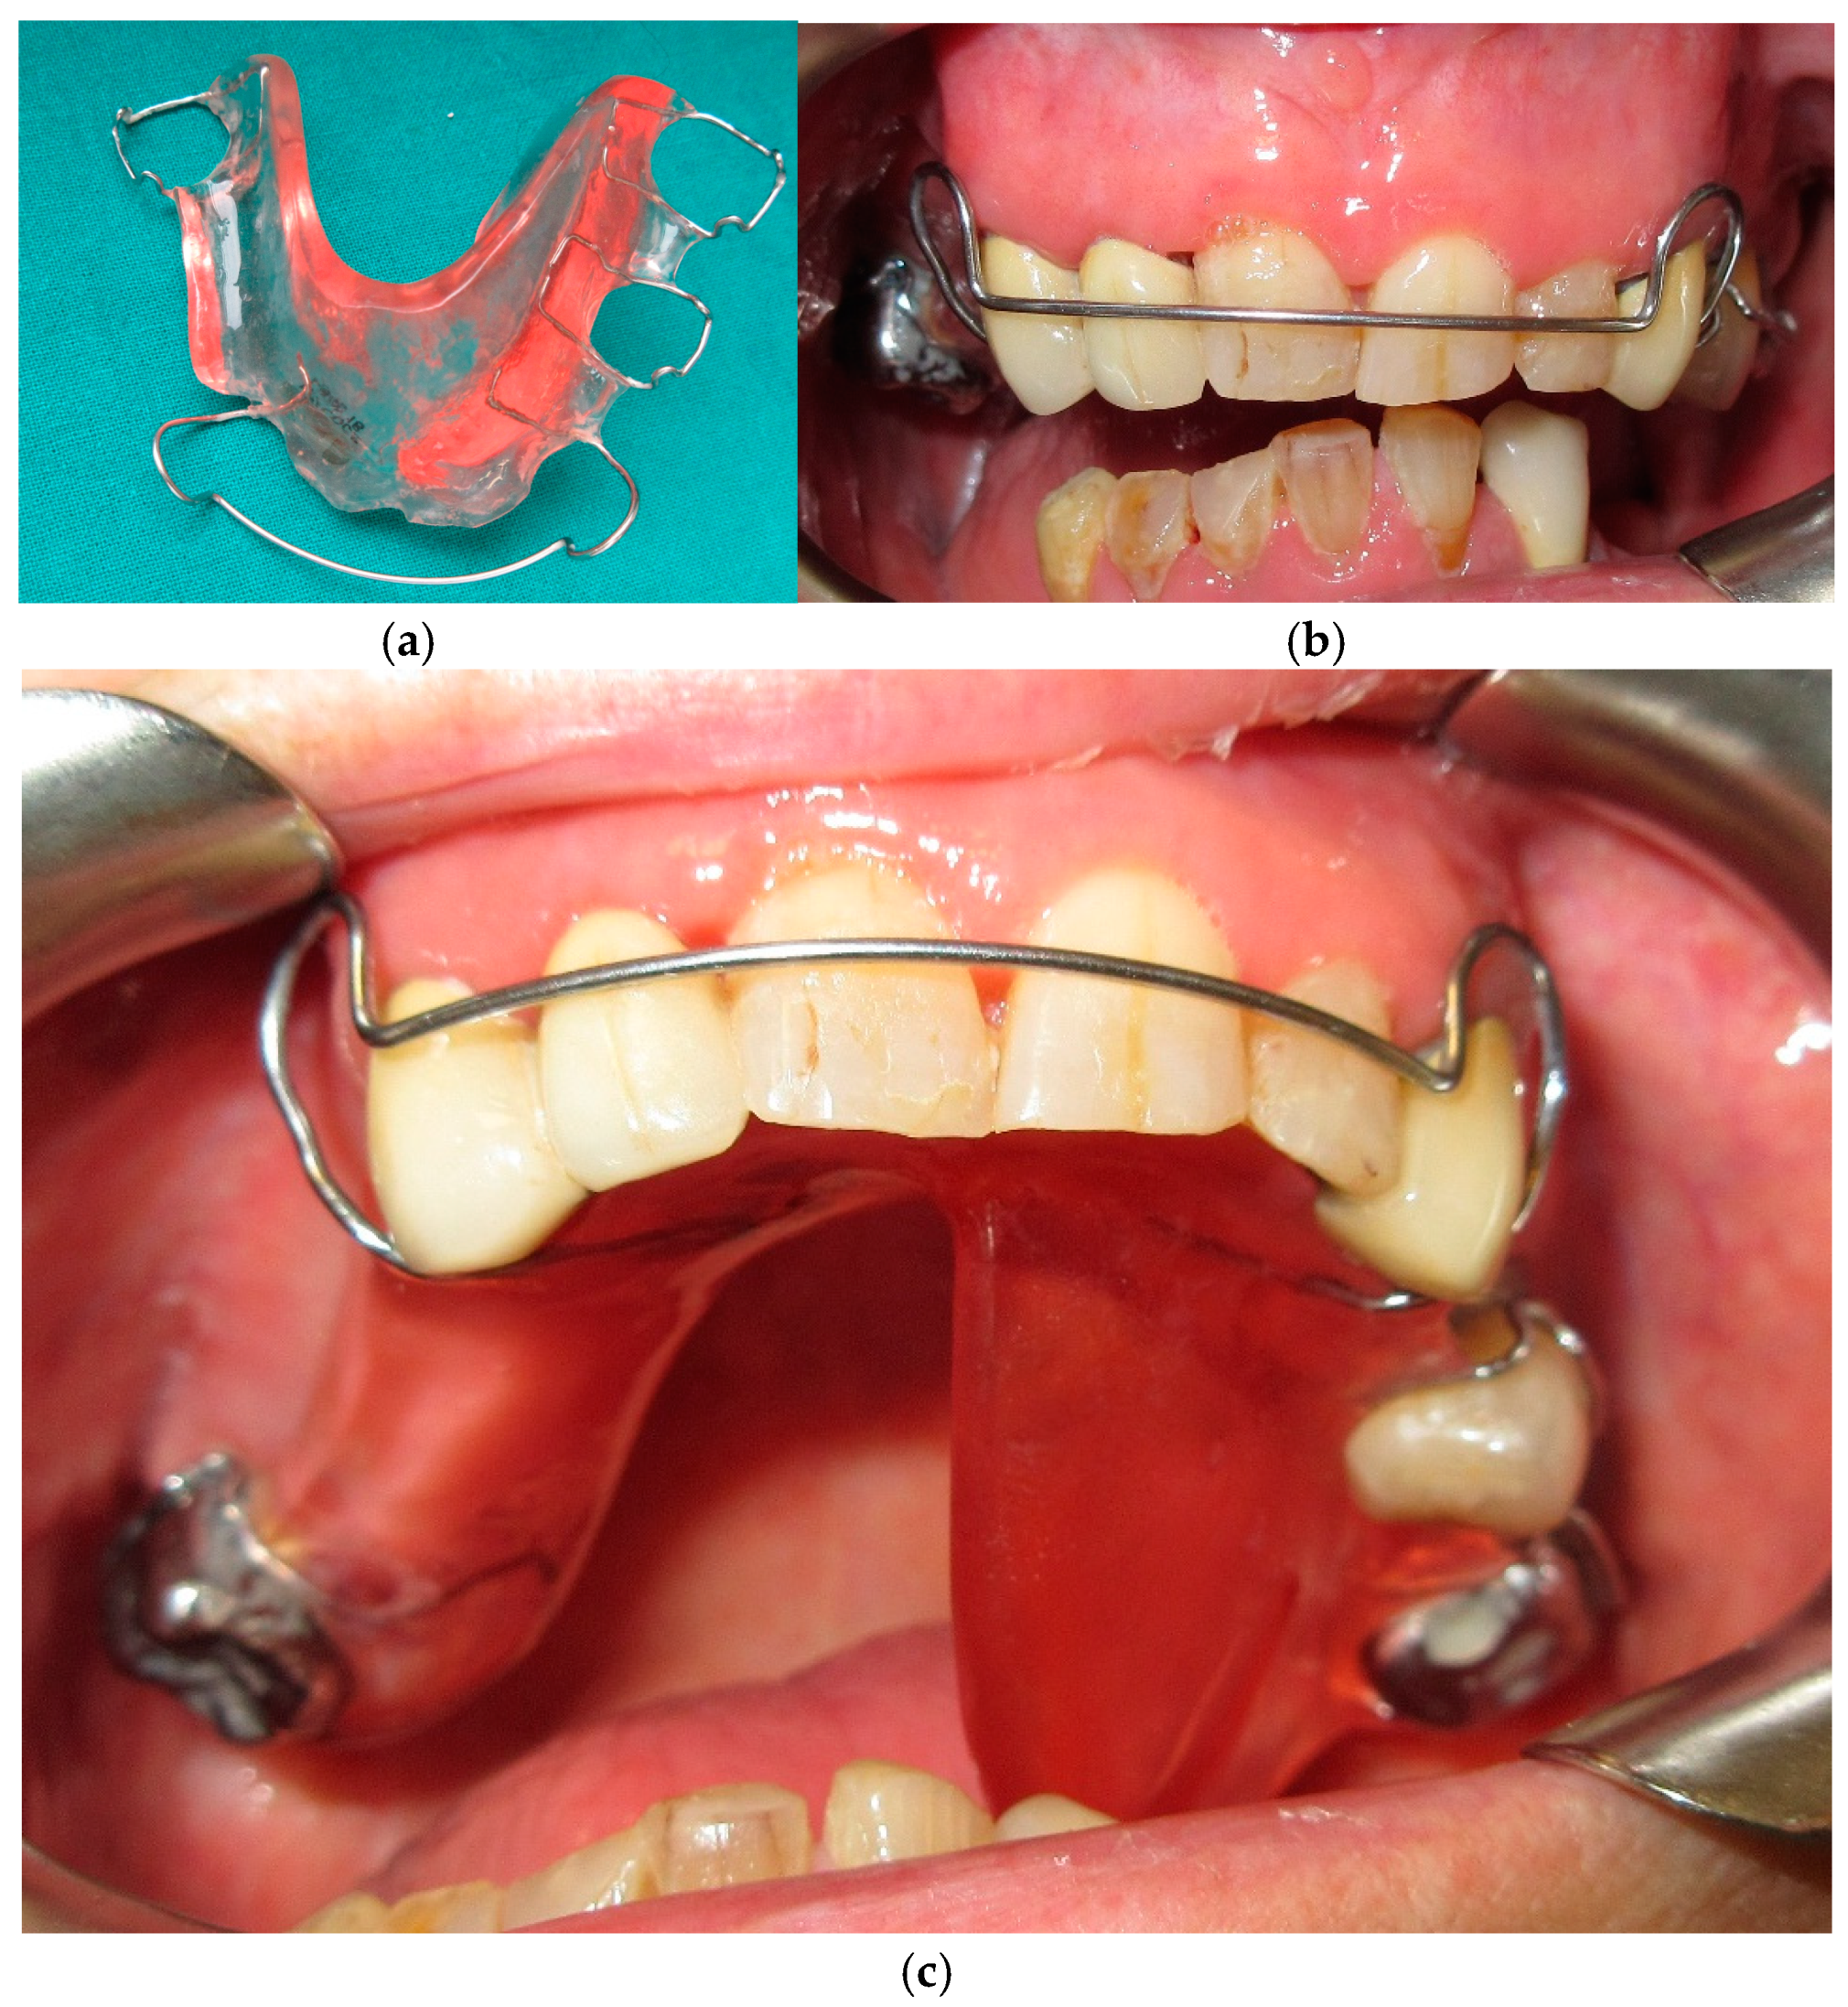

The treatment plan included a transitional occlusal plane guide, an acrylic plate with labial bow for retention on upper teeth with a posterior acrylic process that extends inferiorly (Figure 16 and Figure 17). The contact between the occlusal surface of the remaining mandibular teeth and the acrylic process guides the remaining mandibular segment in a more centric position. This device can be considered a functional device, as it is a tool that works by stimulating the mandible to position itself in a more correct location by blocking the natural deviation thanks to the acrylic process that works as a brake against unwanted mandibular movement. The transitional occlusal plane was then developed in resin with composite teeth and an inferior removable prosthesis equipped with hooks (Figure 18 and Figure 19).

Figure 3. Transitional complete removable denture.

Figure 16. Intermediate occlusal plane guide in extraoral (a), front (b) and palatal (c) intraoral view.